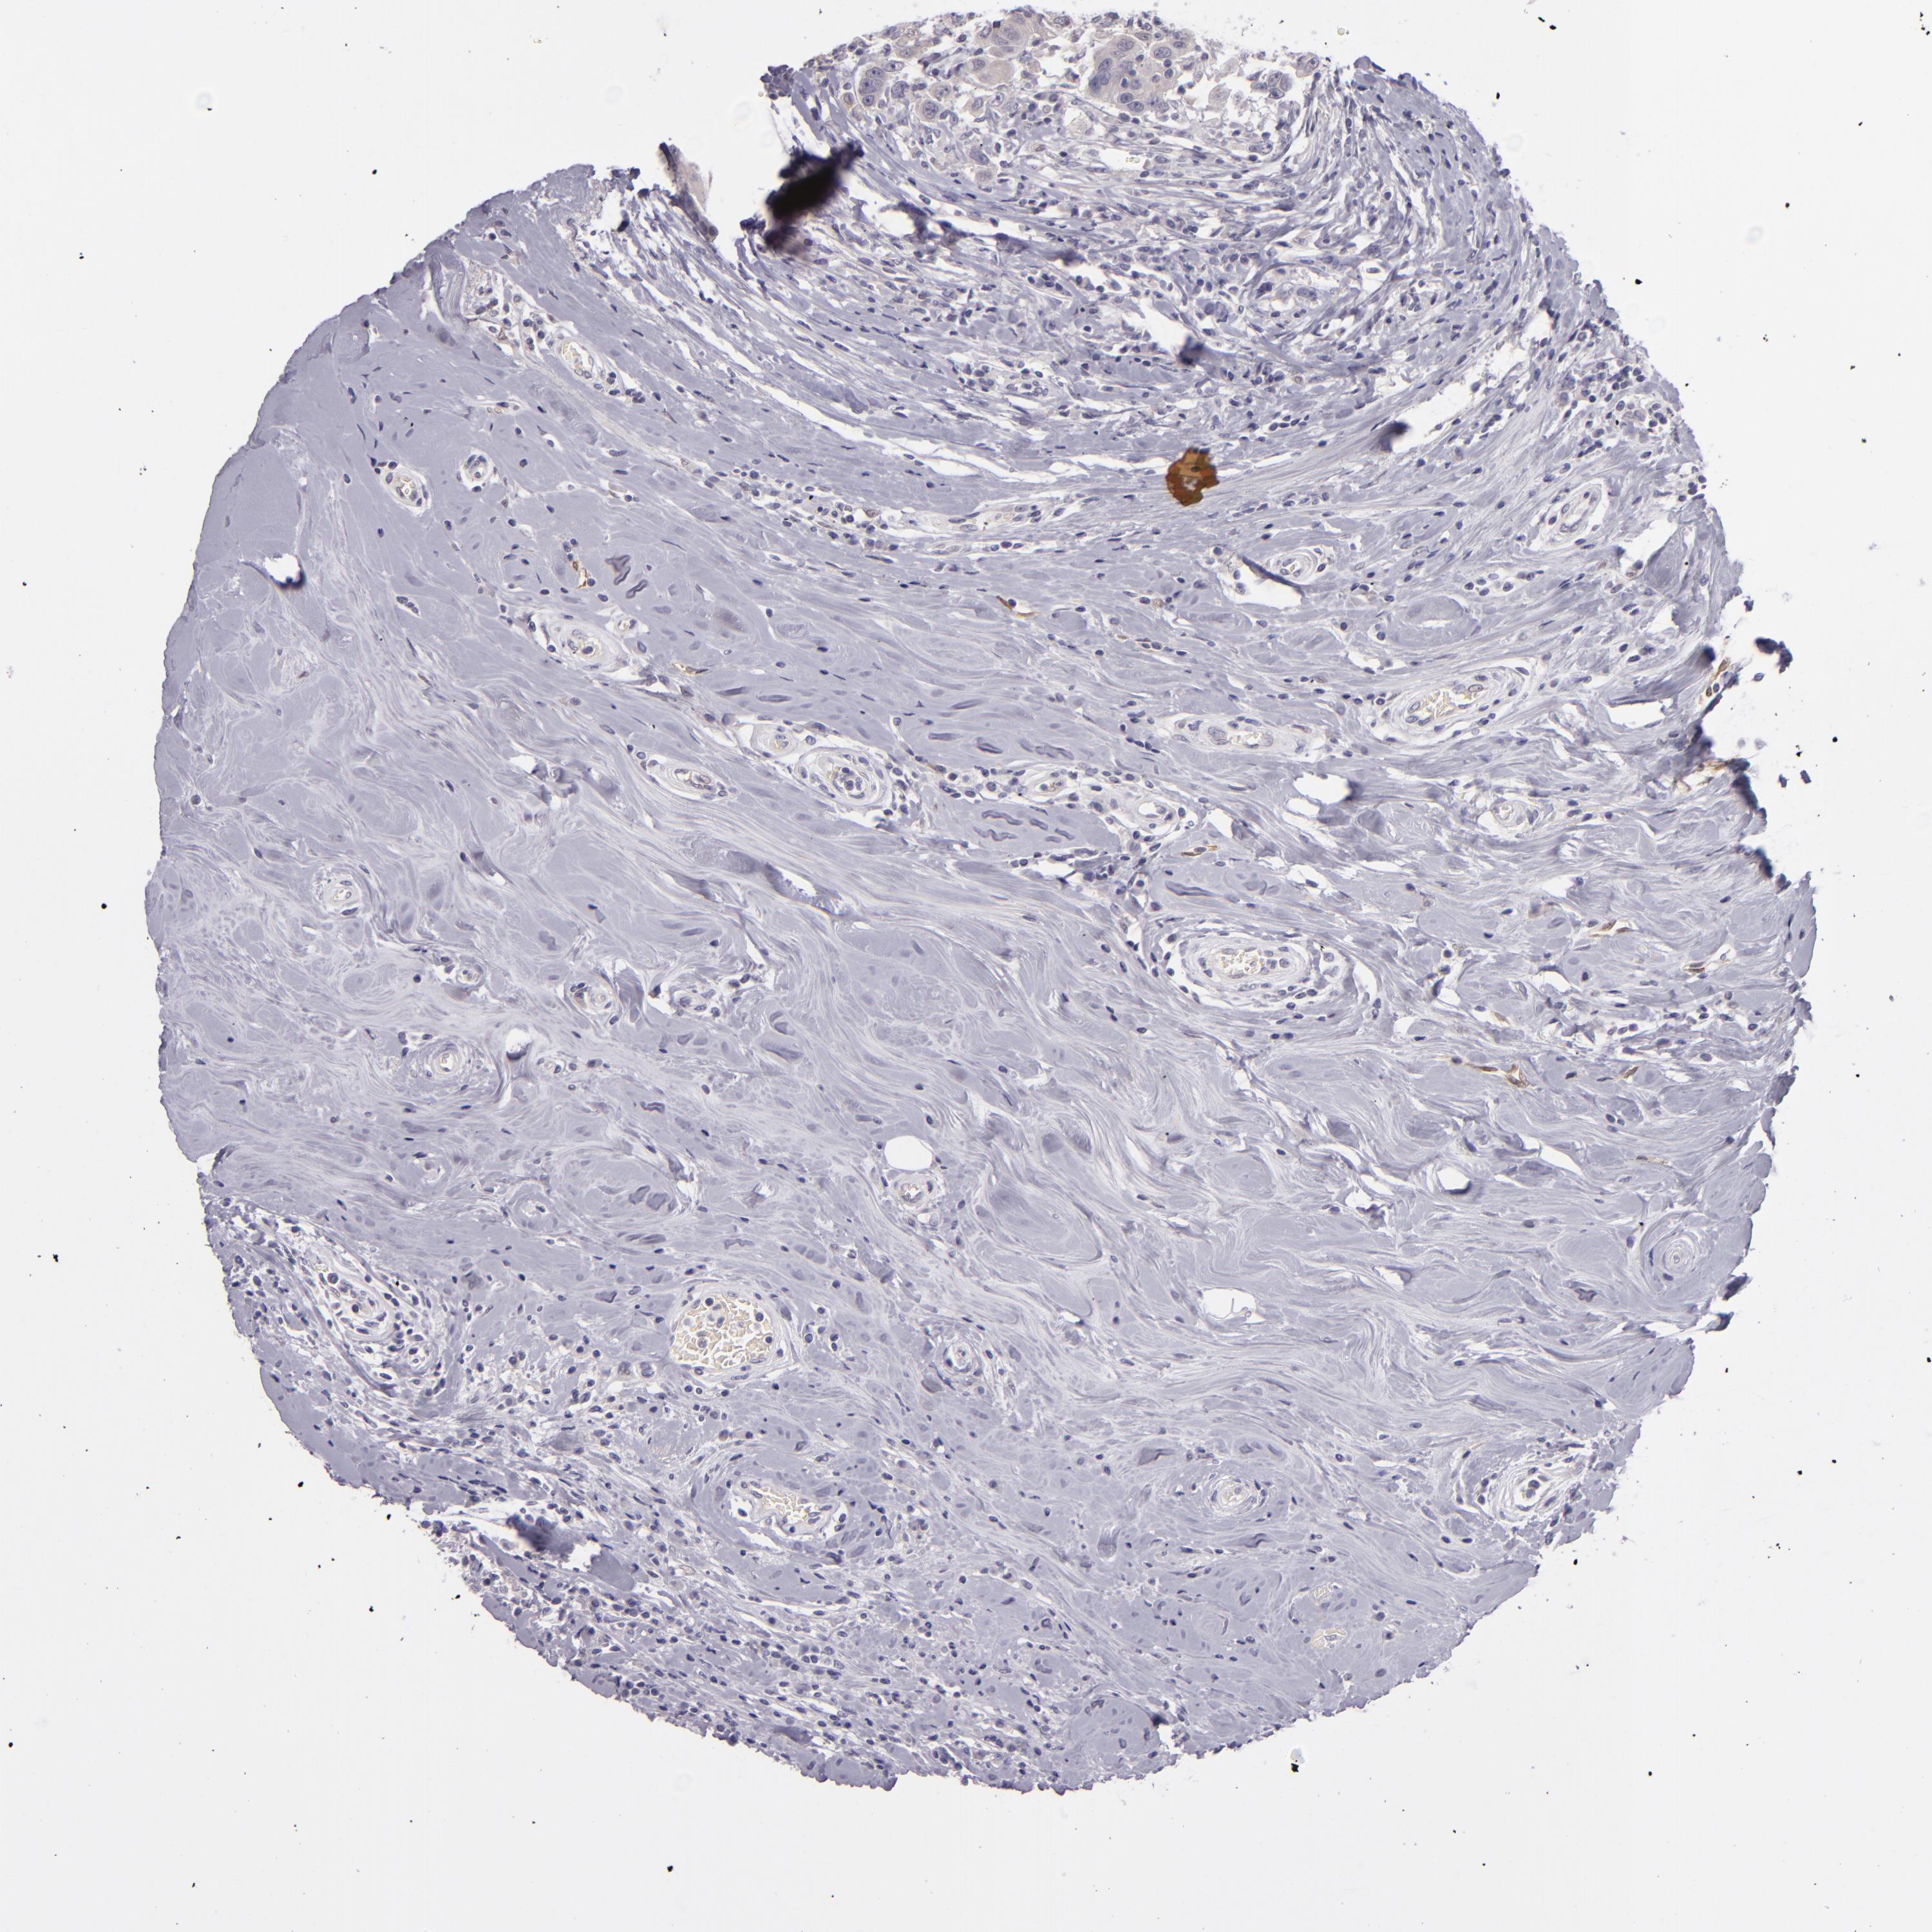

BRCA TCGA BRCA VALIDATION PROTEIN EXPRESSION

ANTIBODIES

AND

VALIDATION